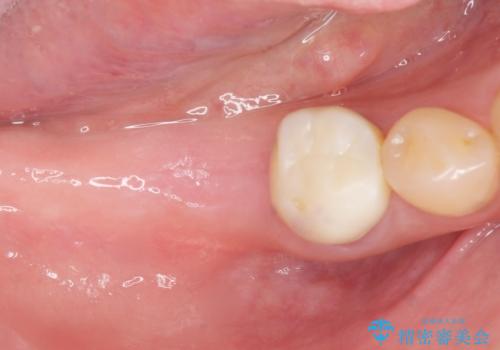

奥歯が割れている 抜歯してインプラントへ 40代女性

- 奥歯の痛みを主訴に来院された患者様です。

精査したところ、右下の奥歯(右下6)は割れており保存不可能な状態でした。

患者様のご希望により、右下大臼歯2本(右下76)のインプラント治療、右下小臼歯(右下5)の根管治療及び補綴治療を行いました。